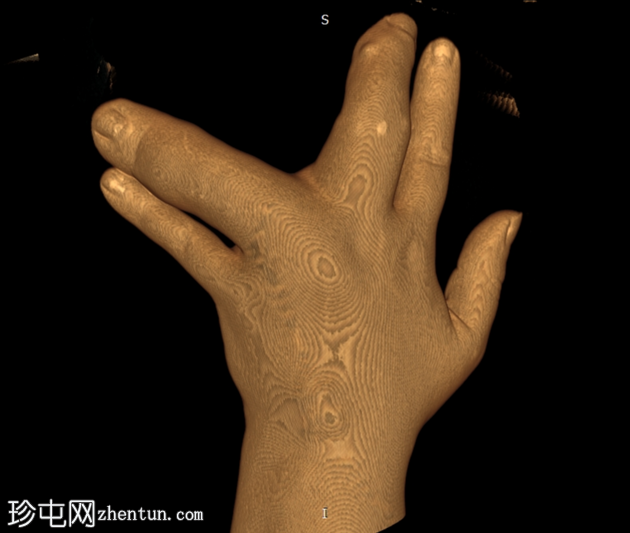

无名指和中指明显增大。患者掌骨和指骨骨质增生肥大,并伴有周围皮下脂肪过度增生。

CT 扫描显示骨质过度生长和肥大、皮下脂肪过度生长以及神经纤维脂肪瘤性错构瘤。

脂肪瘤性巨营养不良症 (MDL) 是一种罕见的先天性疾病。该病与 PIK3CA 基因突变有关。病理学上,脂肪瘤性巨营养不良症表现为所有间叶成分增多,脂肪组织过多,以及其他组织,如骨膜、骨髓、神经鞘、肌肉和皮下组织(局部巨人症)。